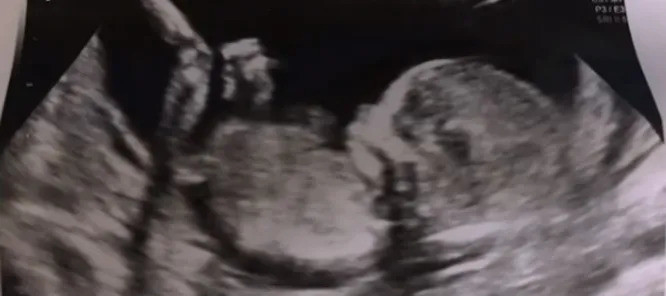

Меган Маркл и принц Гарри пошли наперекор королевской семье. Они публично показали снимок УЗИ, сделанный во время беременности герцогини Сассекской сыном Арчи. Тем самым супруги нарушили строгий королевский протокол.

Снимок появился в четвертой серии документального сериала «Гарри и Меган» на Netflix. Меган рассказала, что их с мужем сблизило желание иметь детей. Они хотели прочувствовать, каково это — быть родителями.

«Мы начали вести дневник в ту минуту, когда узнали, что я беременна. Это было просто: «Дорогой малыш, мы так рады однажды с тобой познакомиться! И мы делали маленькие снимки и вклеивали их в журнал», — вспомнила Маркл.